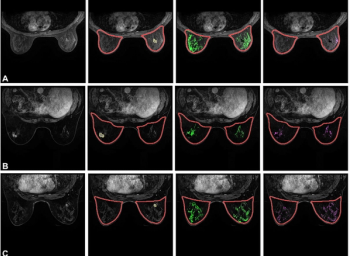

Patients with localized high-risk prostate cancer and midline radiotracer activity in the prostate had over double the incidence of urethral hyperintensity on T2W MRI, according to research presented at the American Society of Clinical Oncology (ASCO) Genitourinary Cancers Symposium (ASCO-GU).